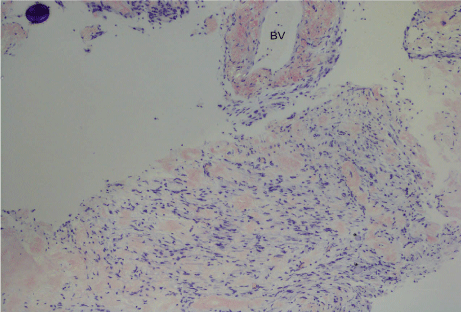

The biopsy from Meckel’s cave showed extensive amyloid deposition both within the nerve with enmeshed myelinated fibres but also in the epineural compartment (Figure 3). There were sparse plasma cells at the edge of the lesion. The extracellular proteinaceous deposit was positive for crystal violet and Congo red staining was positive with typical birefringence and dichroism effects when examined under polarised light. Potassium permanganate pre-treatment only partly obliterated staining with Congo red (Figure 4). Staining for kappa and lambda light chain was not interpretable. Immunohistochemical staining for amyloid-A was weakly positive. The histopathological diagnosis was of an amyloidoma of the trigeminal nerve at the level of the gasserian ganglion.

Figure 4: (Congo red x100): On polarisation, there was focal apple green birefringence of the deposits which appear red on Congo red. A blood vessel (BV) wall is involved at the top right. Two ganglion cells are at the bottom right (*).